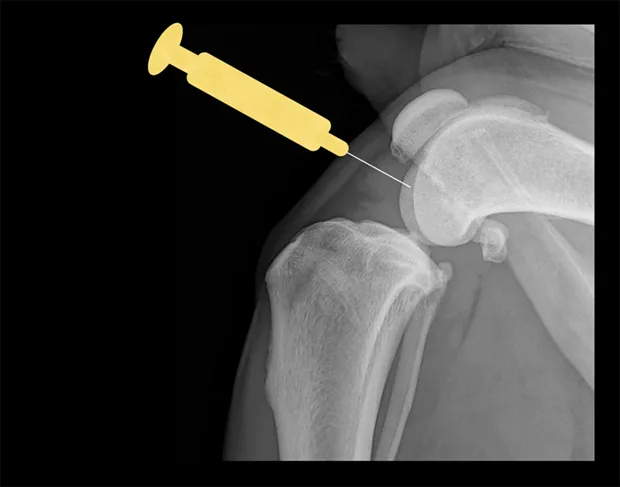

Shoulder

Place the patient in lateral recumbency with the shoulder joint in a neutral position. For large dogs, insert the needle about 0.5–1 cm distal to the acromion process of the scapula in a lateral-to-medial direction; a lateral radiograph of the shoulder joint may help determine the distance from the distal acromion to the joint space. The needle may need to be passed in a slightly dorsal direction to enter the joint. A 1.5-inch needle is adequate for even large-breed dogs.

Lateral view of shoulder. Insert needle just distal to the acromion (yellow dot).